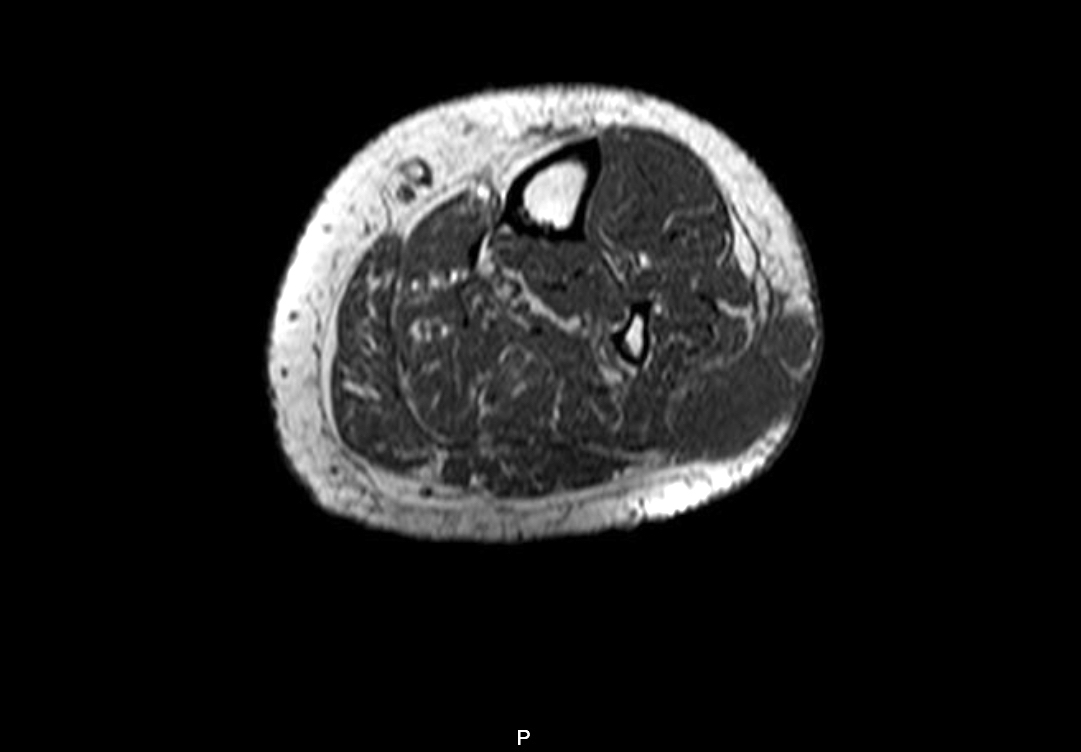

Radiology description

- In MRI T1 weighted sequences, the tumor appears iso or hypointense to muscle

- In T2 weighted and STIR sequences, the tumor is hyperintense with surrounding edema

- In postcontrast sequences, the mass shows heterogeneous enhancement; necrosis is usually present within

- Reference: AJR Am J Roentgenol 2007;189:371

Radiology images